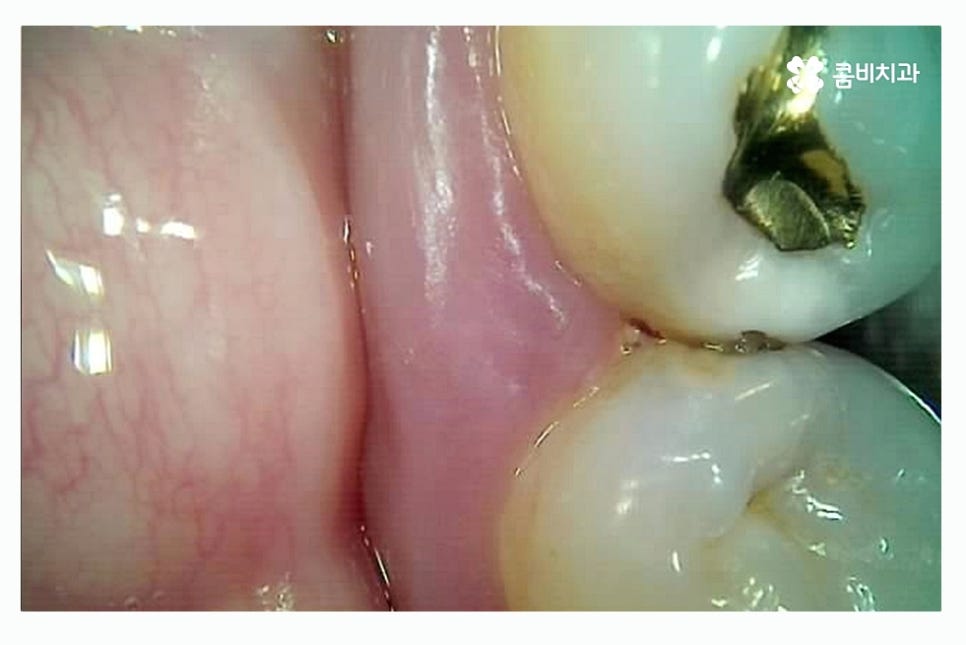

인접면 충치는 초기 발견이 어렵고 치아끼리 맞닿아 있기 때문에

노출이 잘되지 않아서 눈으로도 보기 어렵고

엑스레이를 통해서도 초기에는 확인이 어려운 경우가 많기 때문에

예방을 하는 것이 중요하며 인접면 충치가 발생하면

신경(치수)과도 가깝기 때문에 충치가 조금만 깊어져도

신경치료를 해야 할 가능성이 높아 치아의 수명이 줄어드는 결과를 초래할 수 있어요.